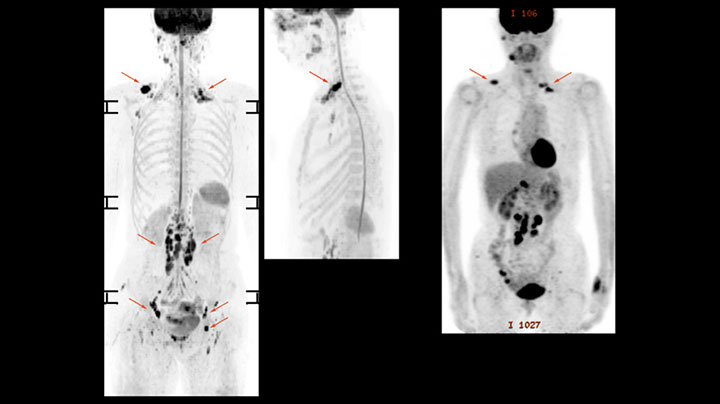

Whole body diffusion

A 61-year-old female with a malignant lymphoma underwent an MRI exam with whole body diffusion weighted imaging (DWIBS) as well as PET. On the images shown, the resolution of DWIBS is better than PET, which allows visualization of the small pelvic lesions and almost no distortion is seen in the neck area.

Prodiva MRI whole body DWI lymphoma, Seirei Mikatahara

Prodiva MRI whole body FDG-PET, Seirei Mikatahara